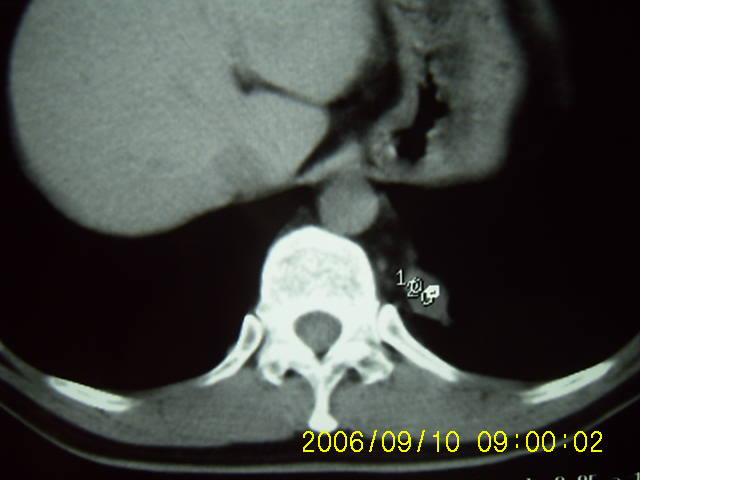

男 43 岁 左侧肩背部疼痛不适一个月,无畏寒 发烧 咳嗽.

左侧脊柱旁沟可见一边界清,密度不均匀之块状影,其内可见水样低密度影。

肺隔离症要考虑;不排除肺内肿瘤。

2、病变位于左肺下叶后段,周围肺组织相对干净,没有明显异常的改变,基本可以排除炎性病变;病变实质内密度均匀,边缘清晰,后下缘与膈脚分界不清晰。各征象均支持肺隔离症。

左下叶后基底段内胸主动脉旁可见一类梭形团块状影,边界较清楚,其内有小结节样高密度钙化影,肿块与胸主动脉可见条状影相连(见下图).

诊断:左下叶肺段隔离症.

左肺下野后侧基底段见结节状肿块影,边界清晰锐利,其内见低密度坏死灶,紧贴胸膜生长,深分叶征不明显,纵隔内无明显肿大淋巴结,临床无咯血病史,所有征像均不支持恶性病变。病变考虑为纵隔内病变,没有增强扫描,定性很困难。